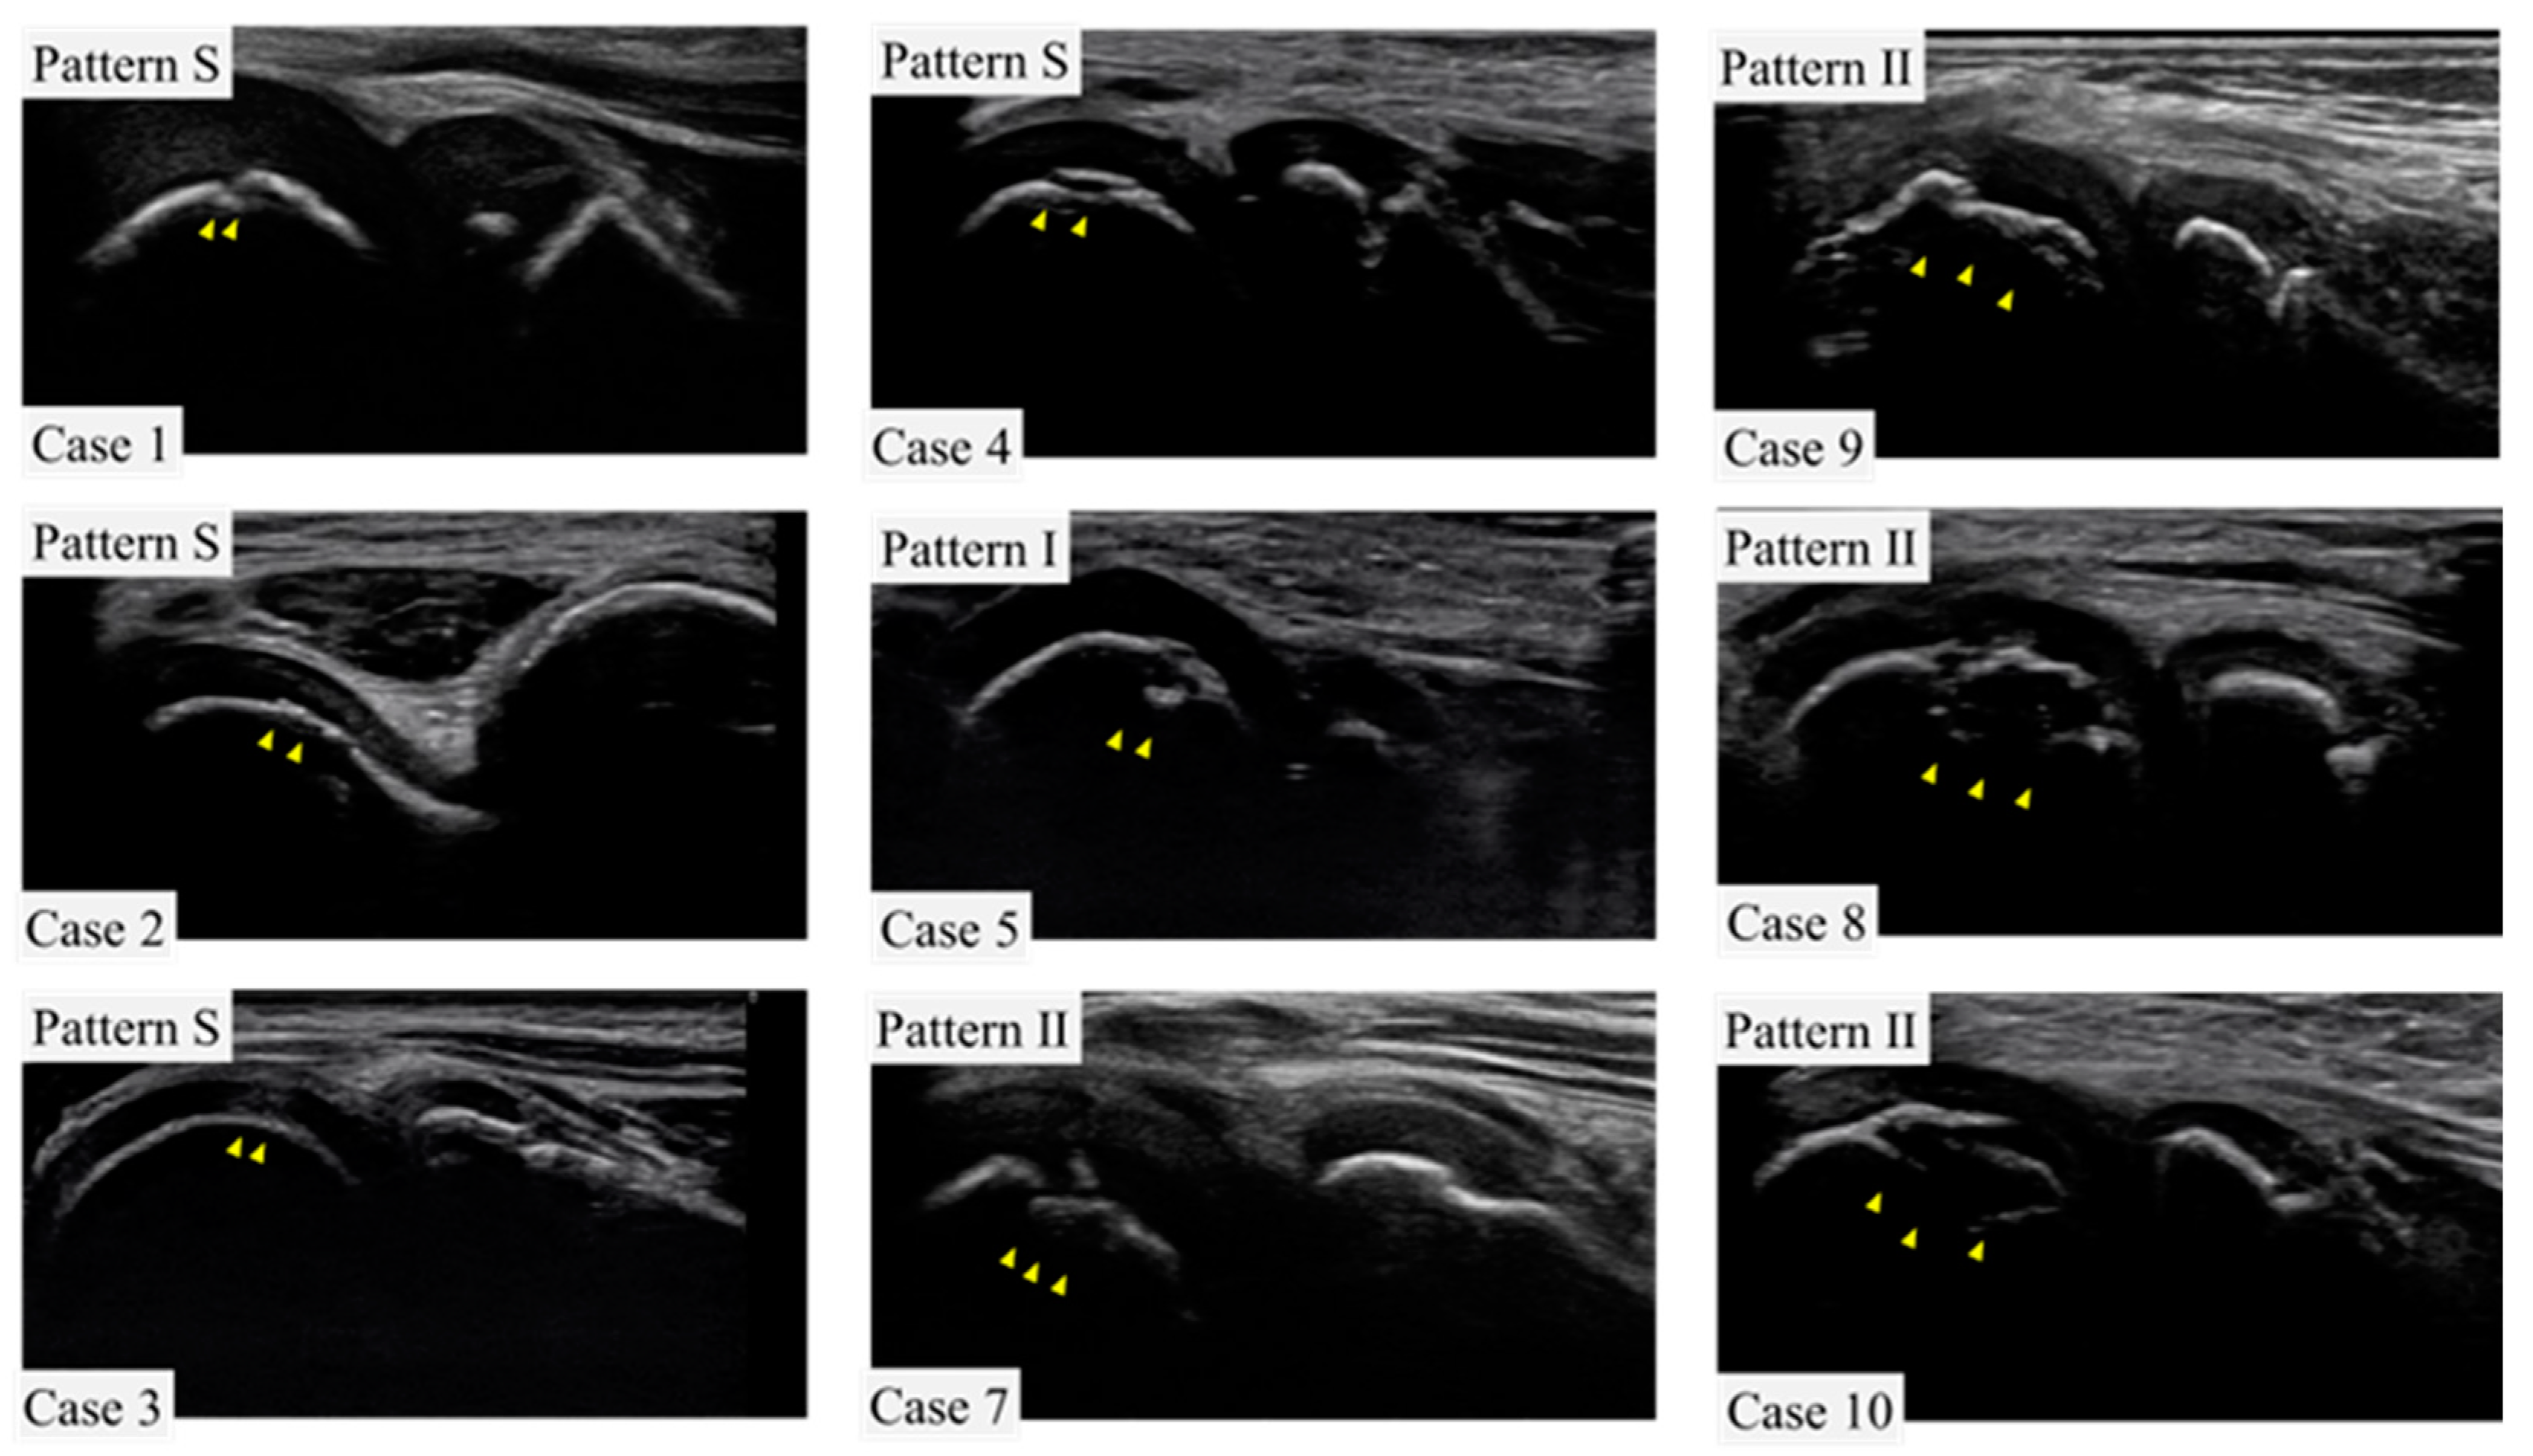

First, the subjects were given a medical questionnaire in which they were asked to provide their name, team, position, and history of elbow pain. Physiotherapists and trainers then assessed the elbow for pain, limited motion, tenderness of the medial epicondyle, tenderness of the humeroulnar or humeroradial joint, tenderness of the olecranon, and instability with valgus stress tests at 30 degrees, 60 degrees, and 90 degrees of elbow flexion for both the throwing and non-throwing sides. The elbow joint was then examined by a physician using ultrasound to confirm the presence of OCD; the Okada’s pattern classification was used to assess OCD [15] (Figure 2). The ultrasound examination focused solely on the lateral side of the elbow, checking both the short axis and the long axis. The equipment used for the ultrasound examination was a portable ultrasonography and an 11-MHz linear array transducer (SONIMAGE MX1, KONICA MINOLTA JAPAN Inc., Tokyo, Japan). The ultrasound examinations were performed by orthopedic surgeons with 3–10 years of experience. For the final analysis, the ultrasound images were interpreted by multiple physicians, including a specialist with over 20 years of experience in orthopedics. In this study, following the pattern classification, those with marginal irregularities were extracted, and the pattern S, which is typically not counted as OCD in a single examination, was also included as OCD for the purposes of this screening.

Figure 2. Characteristic ultrasound images of OCD extracted during the current screening are shown. This study followed Okada’s pattern classification.